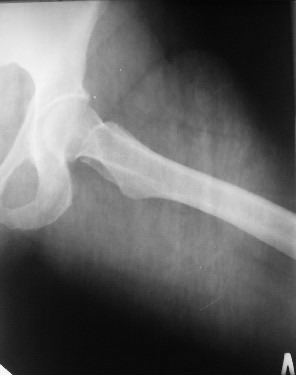

Из анамнеза: в ноябре 2002г. оступилась,упалана трап самолета (на верхней площадке, сразу при выходе из салона) на правый тазобедренный сустав, а затем - вниз на землю на ноги и ягодицы. Потеряла сознание от боли. Доставлена в больницу по месту жительства, лечилась консервативно с диагнозом кокцигодиния.На рентгенограмме от 27.11.02г. вывиха копчика не определяется (снимок идентичен представленной R-грамме от28.11.03г., кроме этого есть нормальная R-грамма копчика в боковой проекции).Через три недели стала ходить, но привести правую ногу в тазобедренном суставе не могла. Сейчас ходит отведя кнаружи правое бедро и голень, как ножку циркуля (фото 1). Неврологических нарушений нет. По просьбе врачаможет на 30-40 секунд поставить ноги вместе (фото 2). При этом испытывает сильную тянущую боль и ощущение "вывернутости" в правом тазобедренном суставе. Эти ощущения заставляют вновь отвести бедро. В положении лежа разогнуть бедро полностью не может из-за болей в ягодичной мышце (фото 3). Сгибание также ограничено из-за болей (фото 4). Отведение в положении лежа возможно в том же объеме, что и стоя (фото 5). Заподозрен старый разрыв правого крестцово-подвздошного сочленения.Выполнено R-исследование и КТ(в приложении). По-поводу деформации лонного сочленения выяснен гинекологический анамнез. Роды одни, нормальные в 22 года. Из роддома выписана на 8 сутки, нарушения походки не было, R-графия таза не проводилась. Вопросы на обсуждение: 1. Диагноз либо алгоритм дальнейшего обследования. 2. Лечебная тактика (в первую очередь возможность и целесообразность оперативного лечения).

Присоединияюсь к мнению д-ра Джолдаса Кульджанова - наиболее вероятно повреждение ацетабулярной губы - acetabular rim syndrome (ARS).

Отсутствие изменений сустава на КТ и обычных рентгенограммах, стойкие боли и ограничение подвижности в суставе - симптомы, характерные для повреждения ацетабулярной губы. ЯМР с контрастом или без должны прояснить картину.

Уважаемый Юрий Алексеевич, сделаны ли пациентке более дистальные срезы КТ с захватом области тазобедренного сустава? Учитывая давность травмы, могли присоединиться и дистрофические процессы в субхондральной кости головки и впадины. Изменения в капсуле будут хорошо видны на УЗИ, особенно в сравнении со здоровой стороной. Эффективность лечебно-диагностического введения гормональных препаратов, на мой взгляд, сомнительна ввиду давности патологического состояния. При такой стойкой и давней контрактуре без операции вряд ли можно обойтись. Под наркозом амплитуда на разгибание должна увеличиться, усилить эффект можно тено-миотомиями заинтересованных групп мышц, капсулотомией + в послеоперационном периоде хорошее консервативное противовоспатлительное лечение с укладками на разгибание.Что мешает приведению пока не ясно, во встретившихся в нашей работе аналогичных ситуациях причиной был формирующийся медиальный остеофит головки, выталкивающий её из впадины.